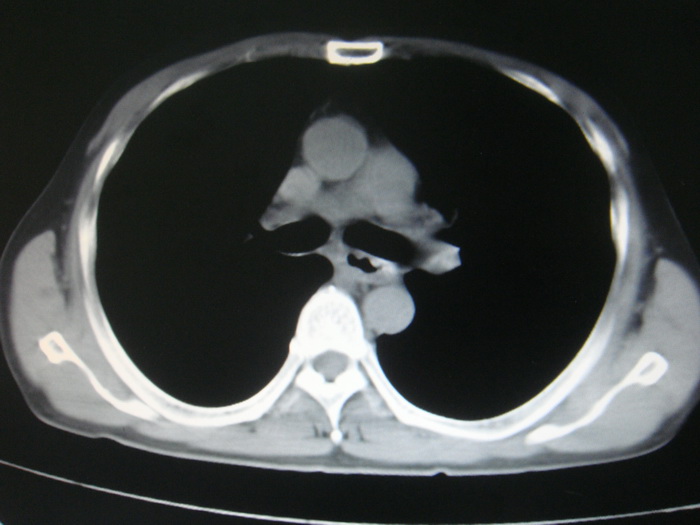

标题: CT28366:男性,45岁,偶尔发现右颈部肿块行胸部CT扫描。 [打印本页]

男性,45岁,偶尔发现右颈部肿块行胸部ct扫描。

两肺多发结节灶及纵膈淋巴结肿大考虑为转移

两肺多发性转移瘤,纵隔淋巴结转移。

两肺多发性转移瘤,纵隔淋巴结转移。食道中上段管壁似乎增厚,作相关检查。

两肺多发性转移瘤,前上纵隔淋巴结转移。

两肺多发性转移瘤,纵隔淋巴结转移瘤。